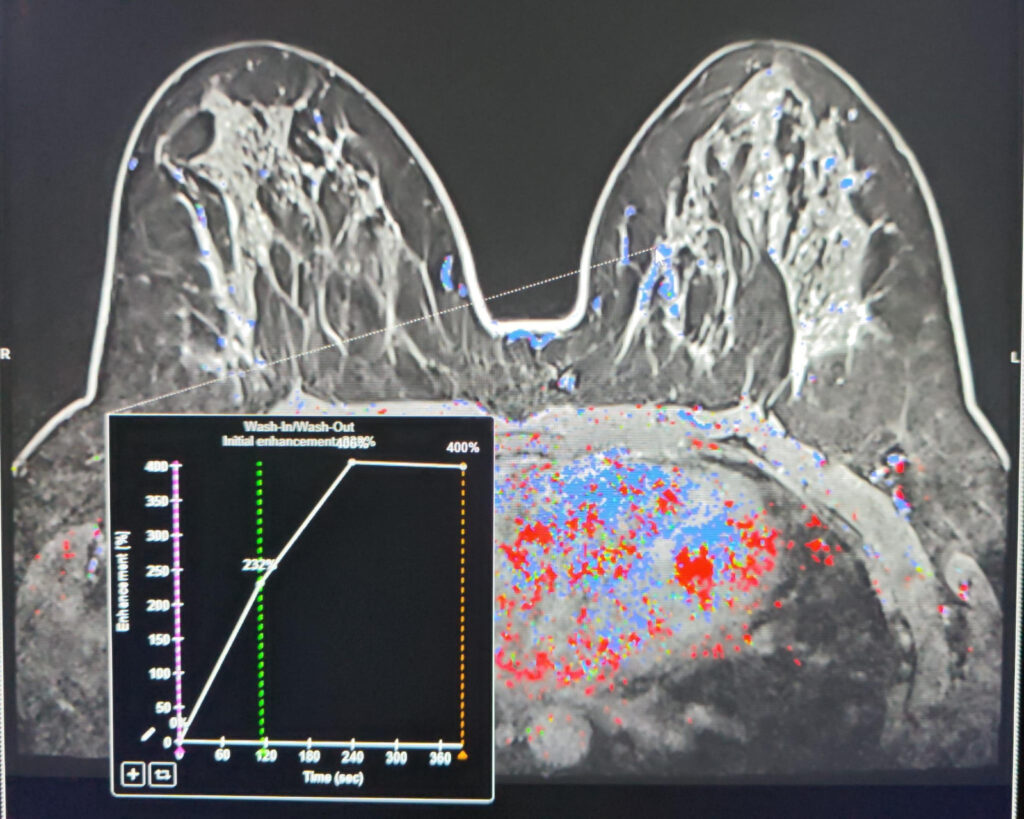

Spitalul Clinic Județean de Urgență „Sf. Apostol Andrei” (SCJU) Constanța a realizat prima puncție mamară ecoghidată cu fuziune de imagini IRM din România, o procedură inovatoare care permite identificarea și biopsierea cu precizie ridicată a leziunilor mamare dificil de vizualizat ecografic.

Intervenția a fost efectuată unei paciente de 39 de ani. Dacă mamografia a evidențiat o leziune suspectă la sânul drept, examinarea IRM a identificat o a doua leziune la sânul stâng. Prima formațiune a fost biopsiată sub ghidaj ecografic, iar cea de-a doua a fost abordată prin tehnica de fuziune IRM–ecografie în timp real, asigurând un grad superior de acuratețe și siguranță.

„Fuziunea imagistică crește precizia diagnosticului și siguranța pacientului, fiind un pas important în senologie la nivel național”, a subliniat Alexandru Gavrilă, medic radiolog.